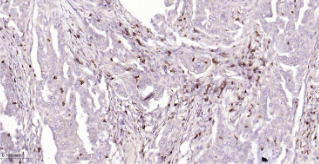

Immunohistochemical analysis of paraffin embedded human lung cancer tissue slide using IHC0501H (Human CD7 IHC Kit).